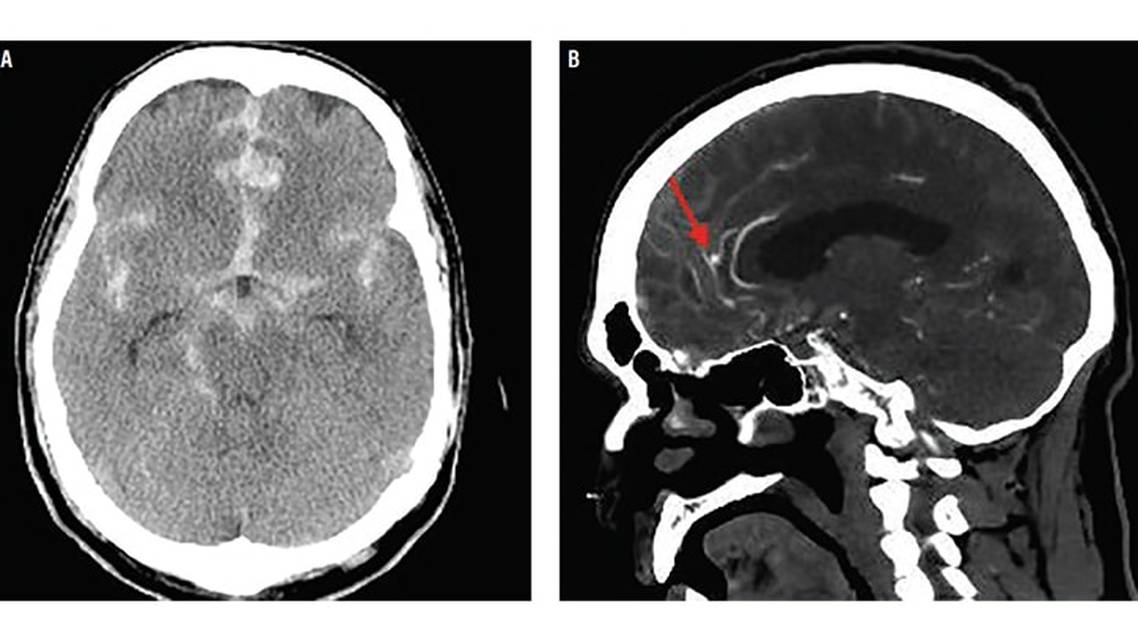

Laboratory test results, including platelet count and coagulation studies were within normal range. Mr Johnson’s head CT demonstrated a Hunt Hess grade 2, modified Fisher 3 subarachnoid hemorrhage (SAH) (Figure 1A). A head CT-angiogram (CTA) demonstrated a 5-mm left pericallosal artery aneurysm (Figure 1B).